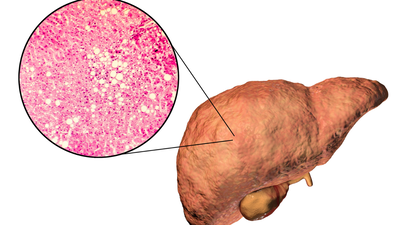

फैटी लीवर रोग एक प्रकार का सार्वजनिक स्वास्थ्य संकट है जिससे केवल कुछ ही लोग बच पाएंगे। हेपेटोलॉजी जर्नल में प्रकाशित एक व्यवस्थित समीक्षा के आधार पर, अब लगभग 38% वयस्कों को गैर-अल्कोहलिक फैटी लीवर रोग (एनएएफएलडी) होने का अनुमान है।फैटी लीवर का निदान, जैसा कि हम में से अधिकांश लोग सोचते हैं, केवल लीवर में वसा का संचय है, लेकिन हमें आश्चर्य है कि यह साधारण वसा के निर्माण से कहीं अधिक है। कार्यात्मक चिकित्सा विशेषज्ञ डॉ. रॉबर्ट डीबीज़ का कहना है कि यह उससे कहीं अधिक जटिल है। उनकी राय में, फैटी लीवर का मुद्दा आपके शरीर के भीतर पोषक तत्वों के साथ क्या हो रहा है, और विशेष रूप से तांबे, विटामिन ए और यहां तक कि फलों में चीनी की ओर इशारा करता है।

सबसे पहले, आइए फैटी लीवर की सरल अवधारणा पर पुनर्विचार करें। डॉ. डीबीज़ बताते हैं कि इस स्थिति का होना वसा के बारे में इतना अधिक नहीं है। बल्कि, “छिपे हुए ट्रिगर्स”, और ये तांबा, विटामिन ए, और फल शर्करा (फ्रुक्टोज़) हैं। लीवर, विष को छानने वाला अंग है, और इसकी मुख्य जिम्मेदारी आयरन को लीवर से बाहर निकालकर रक्त में रखना है, जिससे शरीर गतिमान रहता है।यहीं पर बात भ्रमित करने वाली हो जाती है। यदि आपके पास पर्याप्त तांबा या विटामिन ए नहीं है, तो वह आयरन लीवर में रुक जाता है। लोहे को एक ट्रक के रूप में कल्पना करें जो गोदाम से बाहर नहीं जा सकता। यह इन्वेंट्री लीवर कोशिकाओं को नष्ट करना शुरू कर देती है और वसा जमा करना शुरू कर देती है। तो, आपके लीवर को सहारा देने में, यह केवल कम वसा का उपभोग करने के बारे में नहीं है – यह इस आयरन-शंटलिंग प्रक्रिया को ठीक से काम करने में सहायता करने के बारे में है।

दूसरा, फलों में शर्करा पाई जाती है, जिसे फ्रुक्टोज के नाम से जाना जाता है। कोई सोच सकता है कि फल हर समय स्वास्थ्यवर्धक होते हैं, लेकिन डॉ. डीबीज फैटी लीवर वाले लोगों के लिए एक चेतावनी साझा करते हैं। वह आहार से फलों को पूरी तरह से हटाने की सलाह देते हैं और इसका कारण यह है कि फ्रुक्टोज प्राथमिक रूप से यकृत द्वारा चयापचय किया जाता है और चयापचय में बहुत अधिक ऊर्जा का उपयोग होता है। यदि हम अधिक फ्रुक्टोज का सेवन करते हैं, तो लीवर पर अधिक भार पड़ जाता है और वह “जलने” लगता है।समय के साथ लीवर की कोशिकाएं क्षतिग्रस्त हो जाती हैं, खासकर अगर शरीर में कॉपर और विटामिन ए का स्तर पहले से ही कम हो। यह एक लगातार समस्या पैदा करता है, जिससे फैटी लीवर रोग का चक्र बना रहता है।डॉ. डीबीज़ न केवल समग्र रूप से कार्ब्स को कम करने की सलाह देते हैं, बल्कि विशेष रूप से फलों से मिलने वाली शर्करा से भी परहेज करते हैं। फैटी लीवर वाले व्यक्ति के लिए, फल उतना हानिरहित नहीं लगता जितना दिखता है।यहाँ एक और स्तर है. कॉपर और विटामिन ए शरीर के अंदर उसी तरह से सहयोग करते हैं जैसे हमारे कार्य और दिमाग करते हैं। वे आयरन को लीवर से रक्त में स्थानांतरित करने में सहायता करते हैं। यदि ये पोषक तत्व पर्याप्त मात्रा में नहीं हैं, तो संपूर्ण प्रणाली ध्वस्त हो जाती है। आयरन चिपक जाता है और परिणामस्वरूप, लीवर कोशिकाएं घायल हो जाती हैं और वसा जमा होने लगती है।